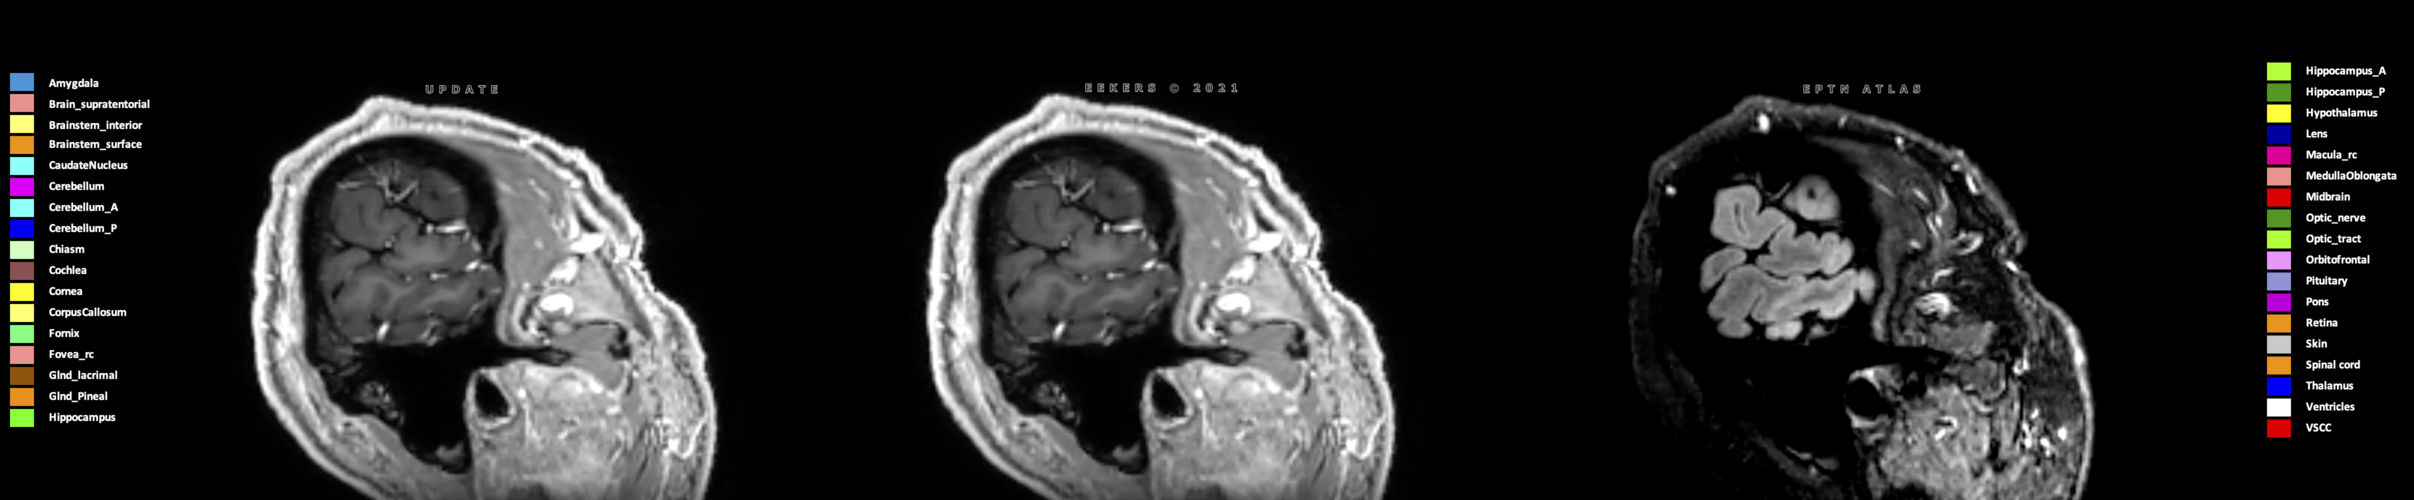

Three-dimensional delineation of the 25 consensus OARs for neuro-oncology are shown on CT (WW/WL 120/40, 3000/600), 3T MR images, (T1Gd, T2FLAIR 1mm) and 7T MR (MP2RAGE 0.7 mm). All are presented in transversal, sagittal and coronal view.